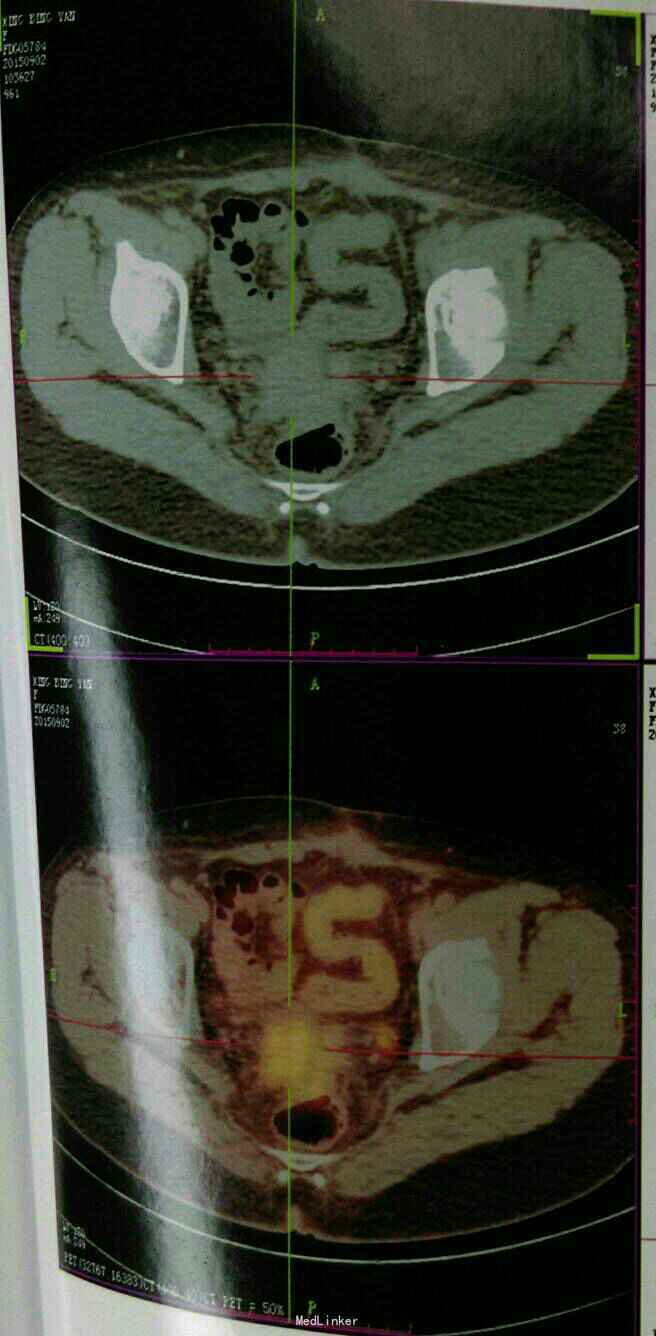

入院查体:腹平软,下腹部可见长约15cm手术切口瘢痕,无压痛,无反跳痛,腹部未扪及包块,肝右肋下、剑突下未及,脾未触及,Murphy征阴性,肝区无叩痛,双肾区无叩痛,移动性浊音阴性,肠鸣音正常,约4-5 次/分。 辅助检查 2015年2月省肿瘤医院术后病理示:右卵巢中分化腺癌,免疫组化:AE1/AE3(+),Ki67(约60%+),CK20(+),Villin(+),CDX2(+),P53(-),WT-1(-),Pax-8(-),TTF1(-),符合转移性腺癌,子宫慢性炎伴鳞状化生,颈管浆膜面及阴道后穹窿:可见腺癌组织,阴道残端及左右宫旁未见癌,左卵巢可见腺癌组织累及,送检网膜组织:可见多个腺癌结节。 PET-CT(2015年9月2日武警省总队医院)示:卵巢癌术后改变:盆腔内软组织肿块,考虑转移。腹膜区及左侧腹股沟多发结节影,考虑转移。

诊断: 卵巢癌术后:腹腔转移 化疗后 治疗:患者家庭经济状况差,患者盆腔病变压迫直肠疼痛伴排便困难,根据情况给予行吉西他滨+顺铂化疗一周期,盆腔转移灶碘125粒子植入术!